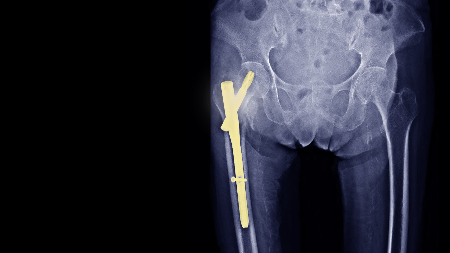

Negative Pressure Wound Therapy Did Not Reduce Infection Rate for Soft Tissue Sarcoma .

Negative pressure wound therapy (NPWT) has been widely adopted to reduce surgical site complications, yet new findings suggest it may not lower infection risk following soft tissue sarcoma resection. In a recent analysis, patients who received NPWT after tumor excision did not experience a significant reduction in postoperative infection compared with those managed with standard wound closure techniques. Soft tissue sarcoma procedures often involve extensive resections and complex wound environments, which may limit the ability of NPWT alone to prevent infection. The findings suggest that while NPWT may still offer benefits in wound management or fluid control, it should not be relied upon as a primary strategy for infection prevention in this setting, emphasizing the need for comprehensive perioperative infection control strategies.